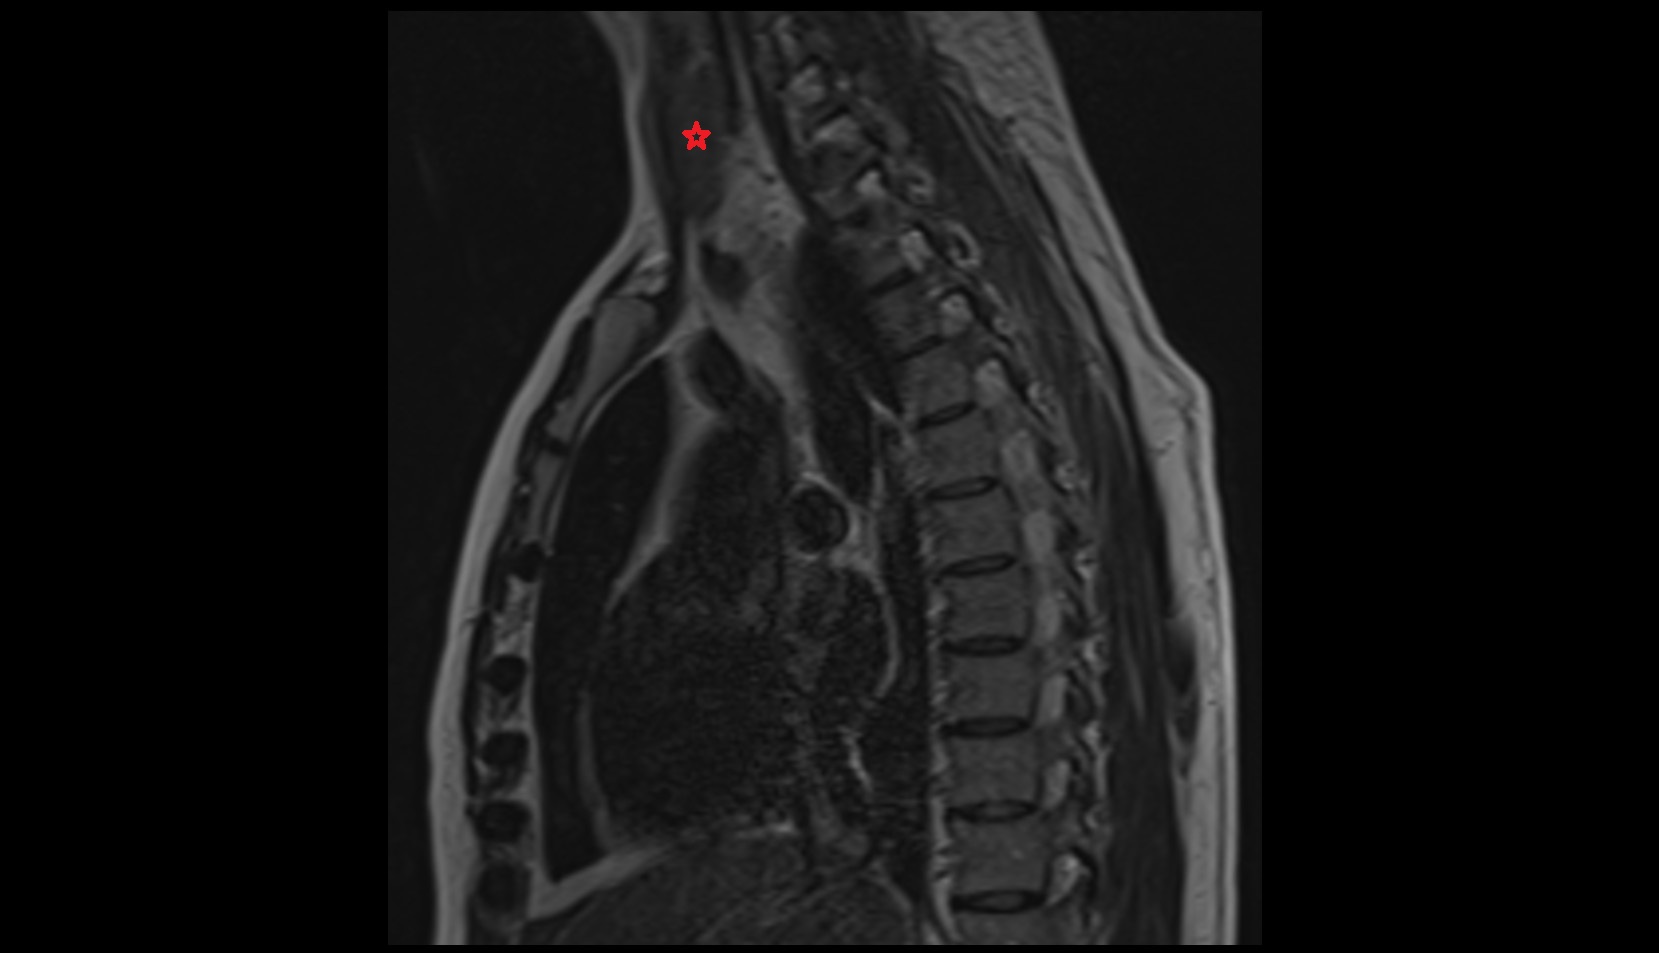

- Spinal cord

- subarachnoid space of spinal cord